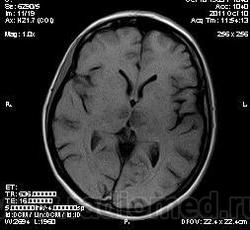

женщина 1963 года рождения. давность заболевания 10 дней.

Билатеральный таламический инфаркт. Либо венозный, либо вследствие закупорки одной из ветвей задней мозговой артерии - ЗМА (вариан развития ЗМА). Но не средней мозговой артерии (СМА). Мне представляеться, что здесь второе... За венозный инфаркт данных не вижу.

Я неприклонен... Инфаркт ЗМА (вероятно, варианта развития левой ЗМА - эмболии, мойа-мойа..).